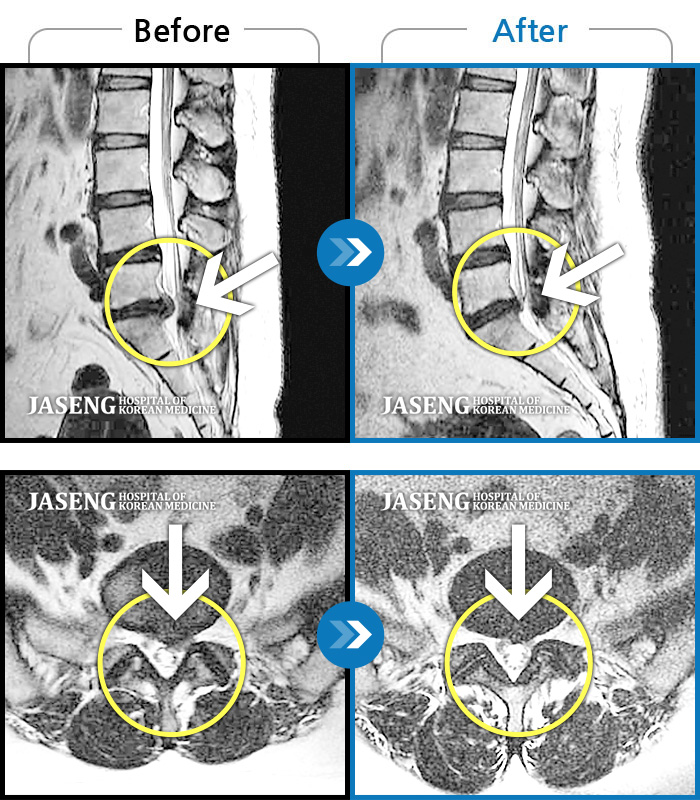

처음엔 이곳저곳 아파서 확실하게 어디가 아팠는지 몰랐는데 사고 후 일주일쯤 될 무렵 MRI촬영후 정확하게 진단을 받았습니다

허리디스크 2단계(초기) 진단을 받긴 했으나 다행히 근육량이 많아 모르고 살았는데 사고로 인해 디스크에 상처가 생겨 힘든 나날을 보내고 있습니다

70대 어머니가 디스크파열로 수술을 당장해야한다는 큰병원의 권유를 뒤로하고 자생을 결정하고 엄봉군원장님을 만났습니다. 두달여 치료받고 많이 호전되었고 갈때마다 진심을 다하시는 원장님으로 인해 정서적인 치료도 받고 있답니다 앞으로도 잘 부탁드립니가!!